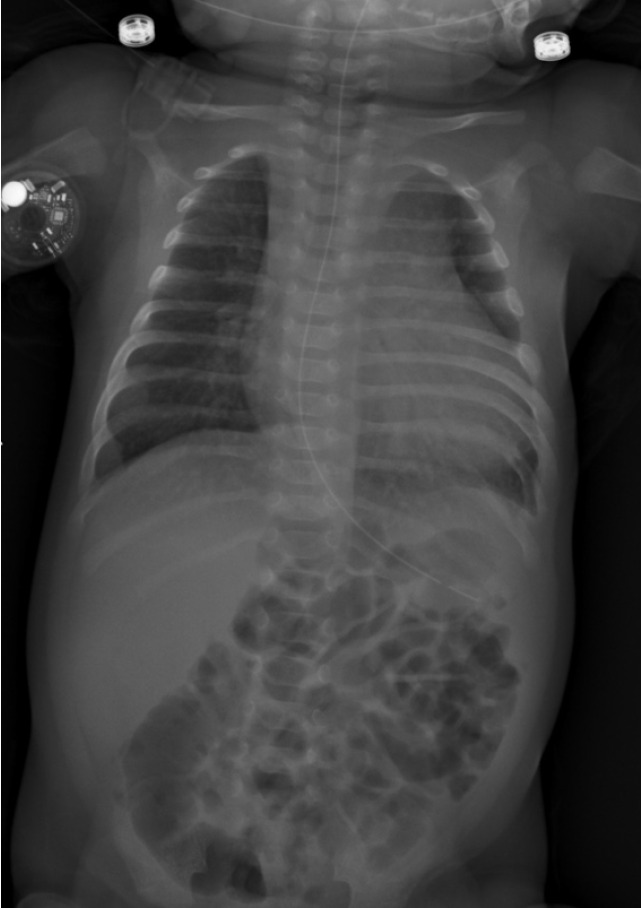

Case summary: The manuscript describes a patient diagnosed with congenital hyperinsulinism (CHI) treated with diazoxide not overlapping with diuretic. He resulted in sudden respiratory distress and therefore was transferred to the Neonatal Intensive Care Unit. The cardiological evaluation showed pericardial effusion and left ventricular myocardial hypertrophy, absent before. In suspicion of an iatrogenic effect of diazoxide it was progressively reduced until stop while introducing diuretic treatment, with resolution of symptoms. Once clinically stabilized, an 18 fluoro-diydroxy-phenylalanine positron emission tomography/computed tomography (PET/CT) was performed to differentiate between a focal or diffuse form of CHI. The PET/CT highlighted the presence of a single focal accumulation of the tracer located in the pancreatic tail, consistent with a focal form of hyperinsulinism. At the age of four months, the patient underwent a distal pancreatectomy with histological confirmation of a focal form of nesidioblastosis, resulting in a curative operation.